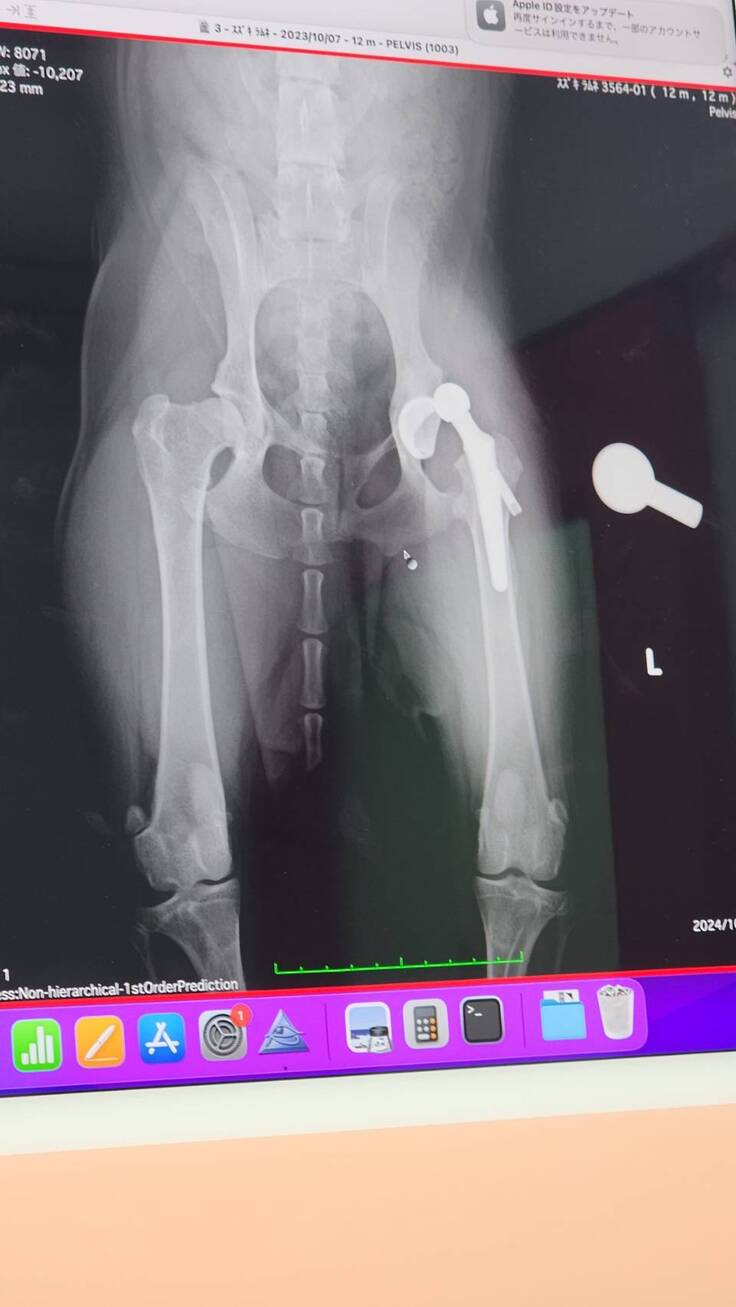

退院予定日の2日前に病院から連絡が入り、人工股関節が脱臼してしまっていると報告を貰いました。

緊急で昨日再手術があり本日10/13が退院予定日でしたが、病院で現状と今後の説明がありました。

もともと亜脱臼状態で生活していたため筋肉もそのように作られており人工股関節に違和感がありはずれてしまった。さらに人が好きすぎて看護師さんを見ただけでもはしゃいでおりそのタイミングで外れてしまった。いくつかの過程を聞き最後に。。。